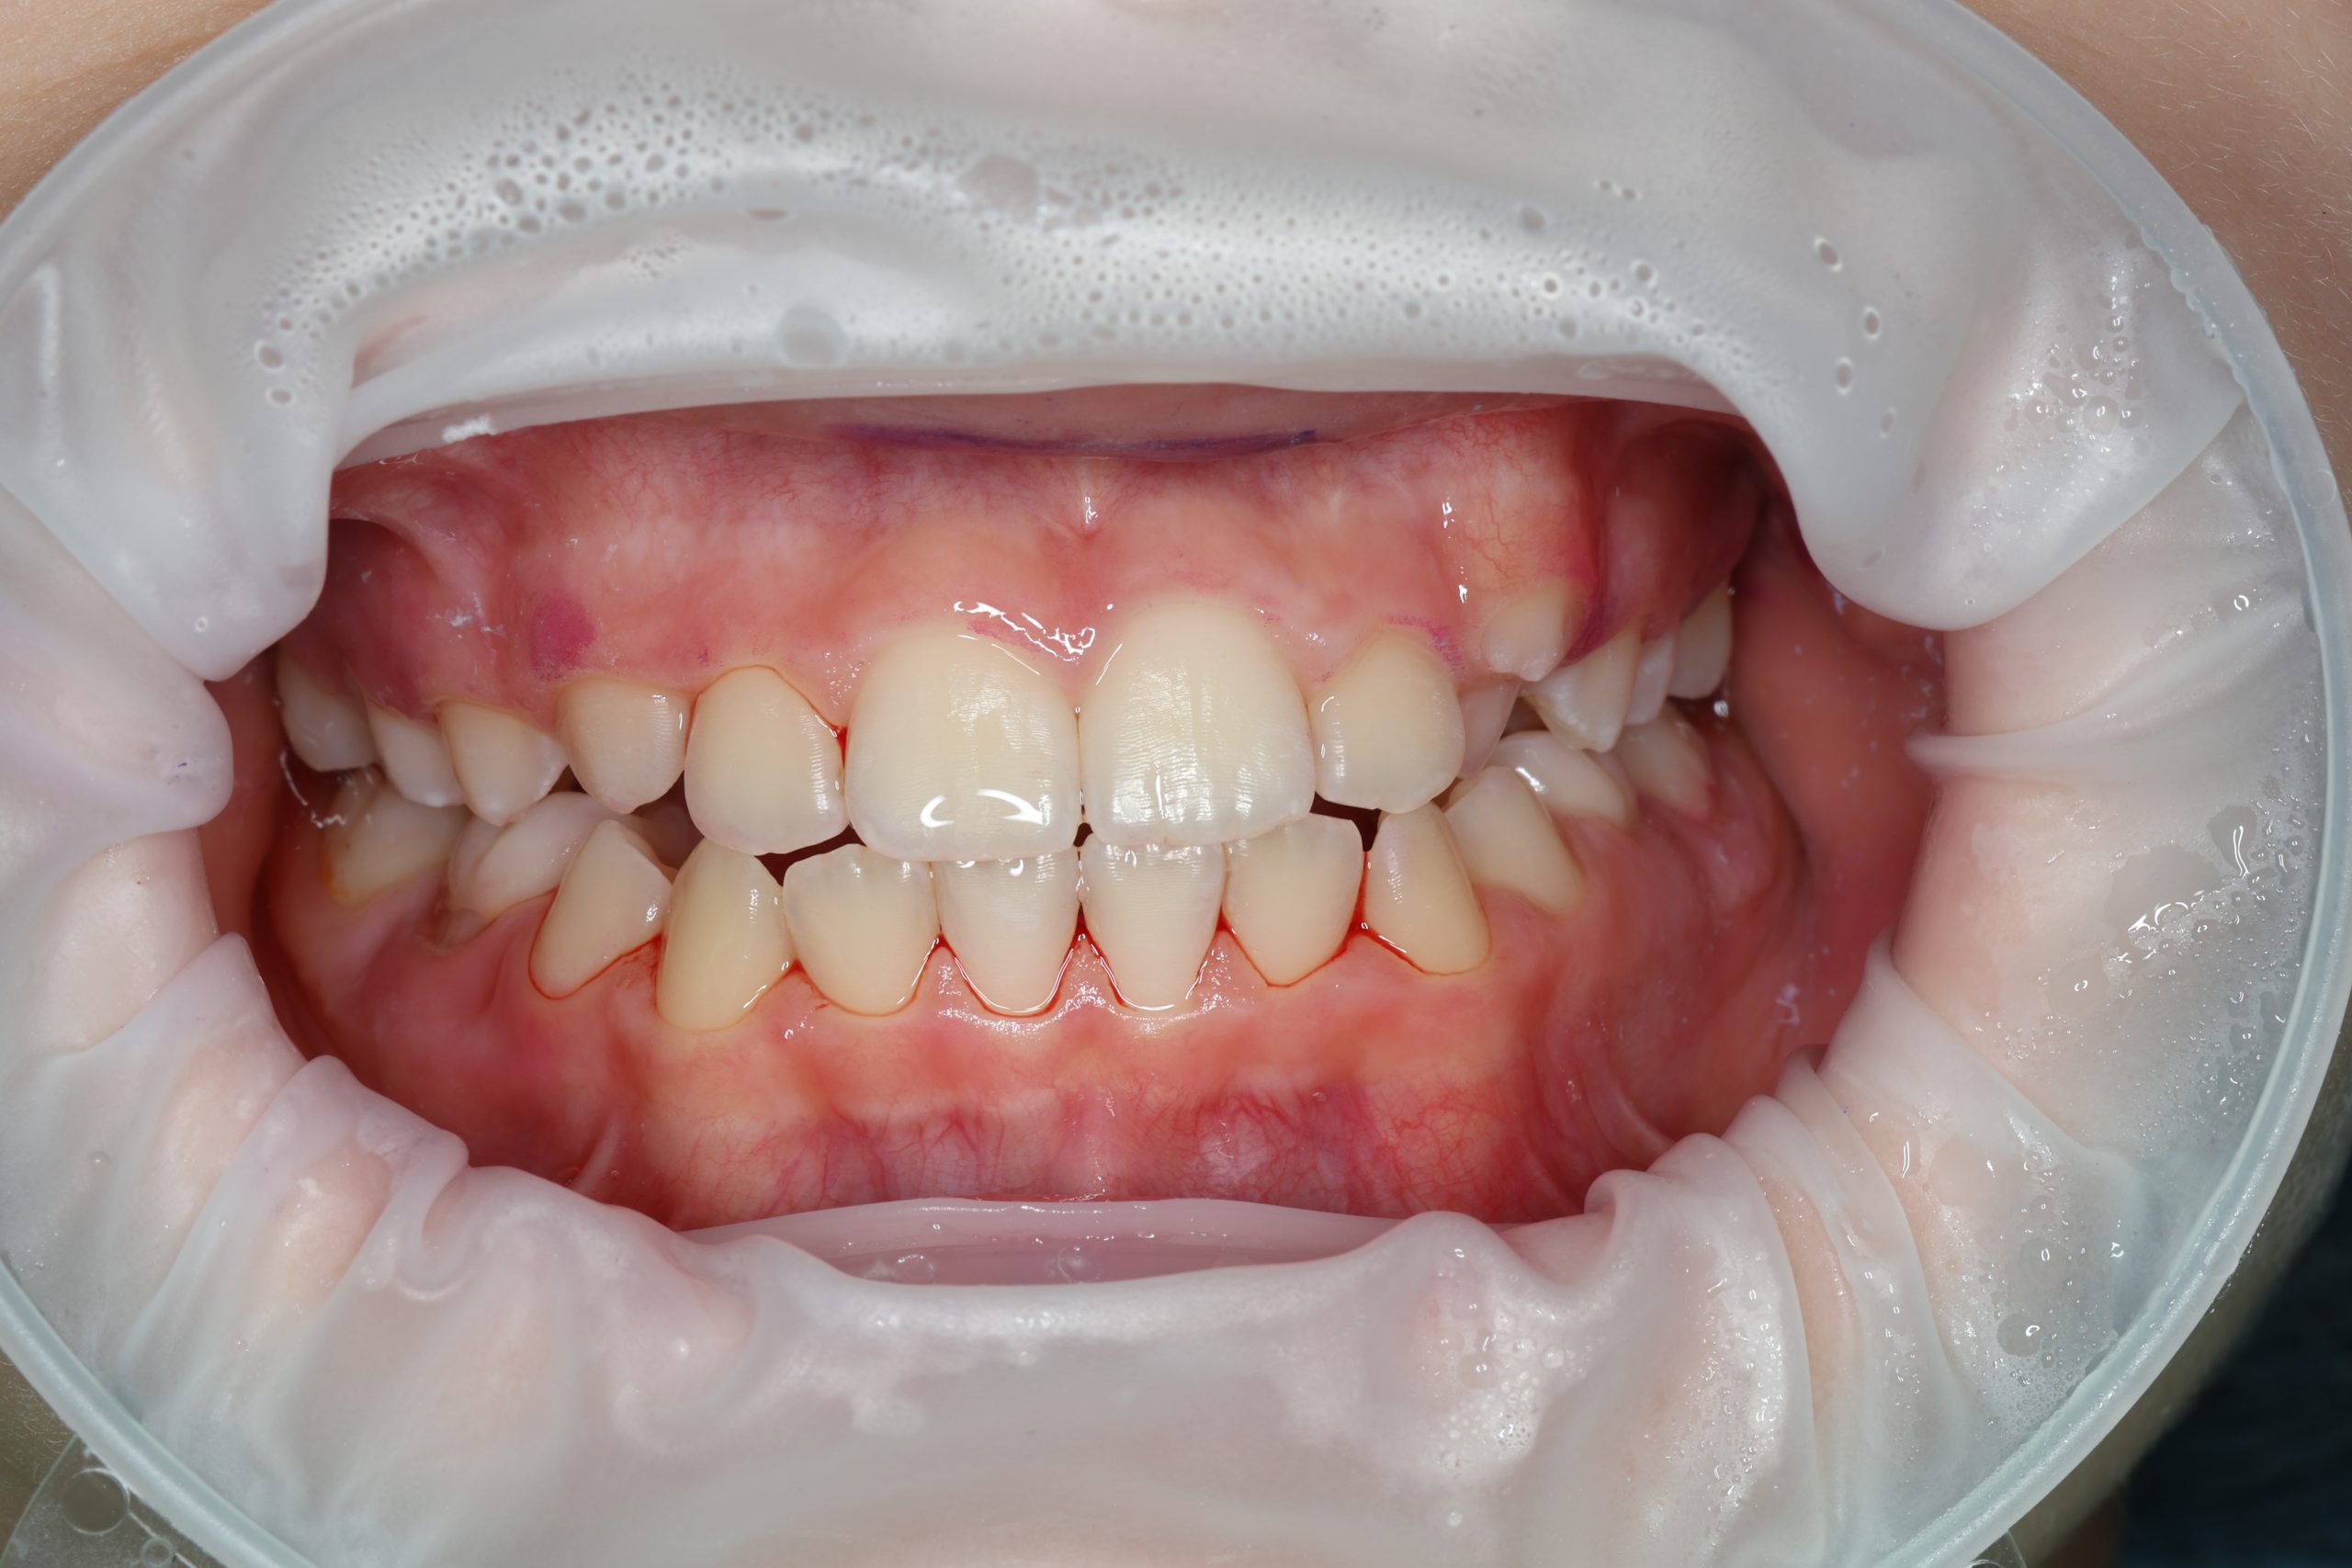

GBT (Guided Biofilm Therapy) is a modern, safe protocol for professional dental cleaning developed in Switzerland. For children, we use it to gently remove plaque, prevent cavities, and teach proper brushing — with plaque-disclosing dye and AirFlow technology starting from age 4–5.

- Detailed Examination

We examine the condition of teeth, gums, and bite. - Plaque Disclosure with Special Indicators

Any tartar is removed gently and painlessly. - Final Check-Up + Fluoride Protection

We ensure the teeth are clean and free from early caries (even in the spot stage), then apply fluoride varnish to protect and strengthen enamel. - Personalized Recall Plan